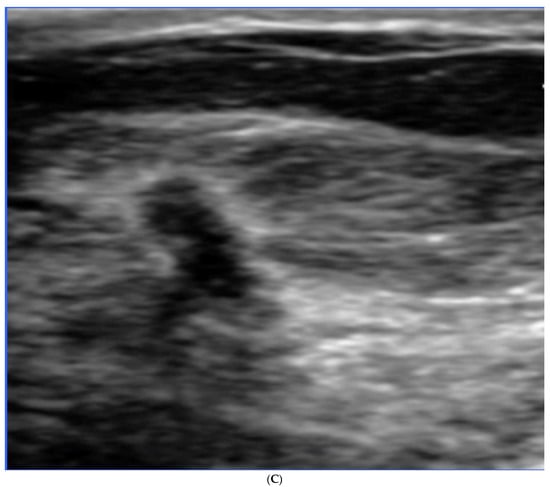

5. Ultrasound (US)